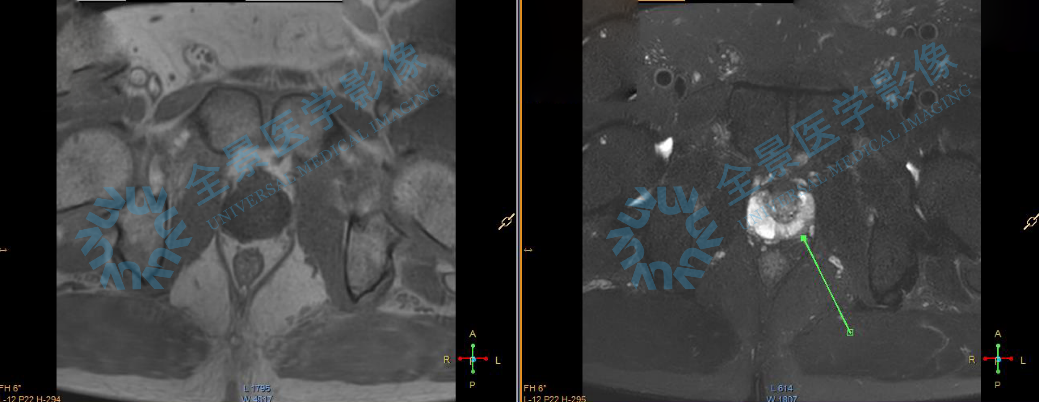

影像结果显示:张先生的前列腺已出现萎缩,结合 TPSA 等肿瘤标志物检测,医生给出判断——虽然 40 岁出现前列腺萎缩在时间上偏早,但目前尚无恶性病变证据,需要定期随访。

前列腺萎缩通常与年龄增长相关,但在 40 岁出现确实偏早。这种情况可能与激素水平变化、慢性炎症或局部血液循环障碍有关。虽然检查排除了恶性肿瘤,但这种早期变化仍是一个健康警示,提示需要开始关注并管理前列腺健康。